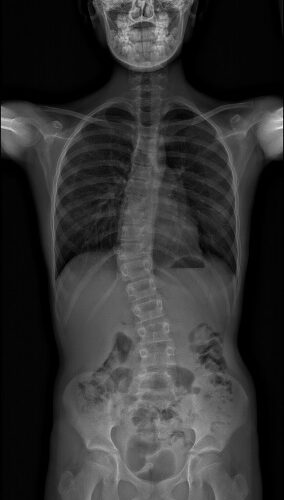

Une scoliose est une déformation de la colonne vertébrale dans les 3 plans de l’espace.

Une scoliose peut facilement être dépistée en faisant pencher votre enfant en avant. Si une bosse apparait, ou s’il existe une asymétrie de la colonne vertébrale, mieux vaut consulter votre médecin pour qu’il examine votre enfant et lui fasse faire une radiographie. Il est recommandé de surveiller le dos des enfants 1 à 2 fois par an, en particulier s’il y a des antécédents de scoliose dans la famille.